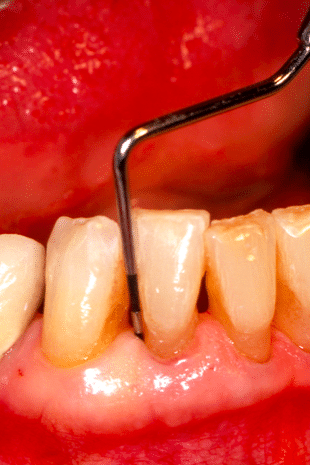

Misurazione tramite sonda della tasca parodontale

Gengive

Tasche gengivali e parodontite o piorrea